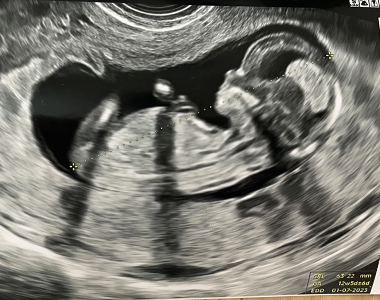

Petra (21. týden těhotenství)

je neuvěřitelné, jak ten čas běží. Příští týden Vánoce, miminko kope čím dál víc a konečně se mi blíží druhotrimestrální screening.